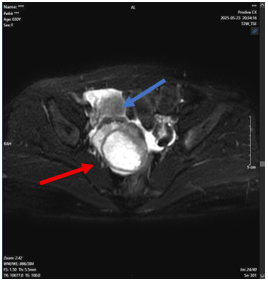

Để làm rõ tổn thương, bệnh nhân được chụp MRI vùng chậu, kết quả:

- Buồng trứng phải kích thước khoảng 34 × 25 mm, trung tâm có ổ ngấm thuốc kém

- Cạnh buồng trứng phải có khối kích thước khoảng 51 × 47 mm, trung tâm dạng dịch